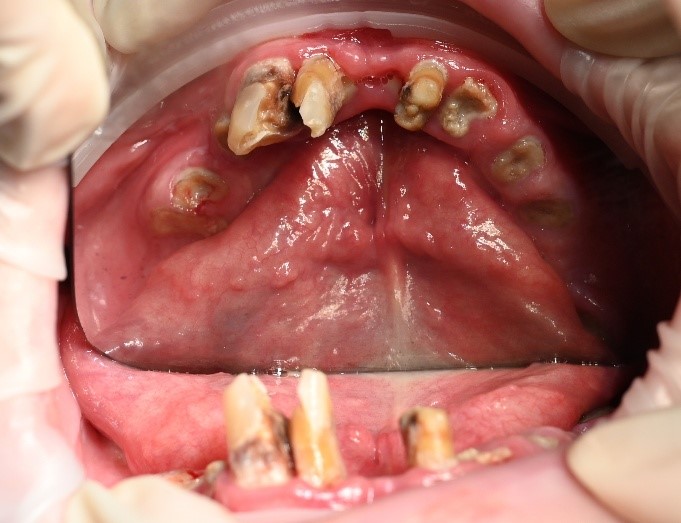

We carried out a comprehensive clinical assessment and gathered detailed diagnostic records, including:

• clinical photographs

• intraoral scans and photos

• OPG x-ray

• CBCT scan

• digital implant planning records

These records allowed us to carefully evaluate bone levels, gum health, and ideal implant positioning.

Although the patient showed moderate bone loss in certain areas and signs of previous chronic infections, his overall bone quality remained suitable for implant treatment. Importantly, there was no active infection at the time of surgery.